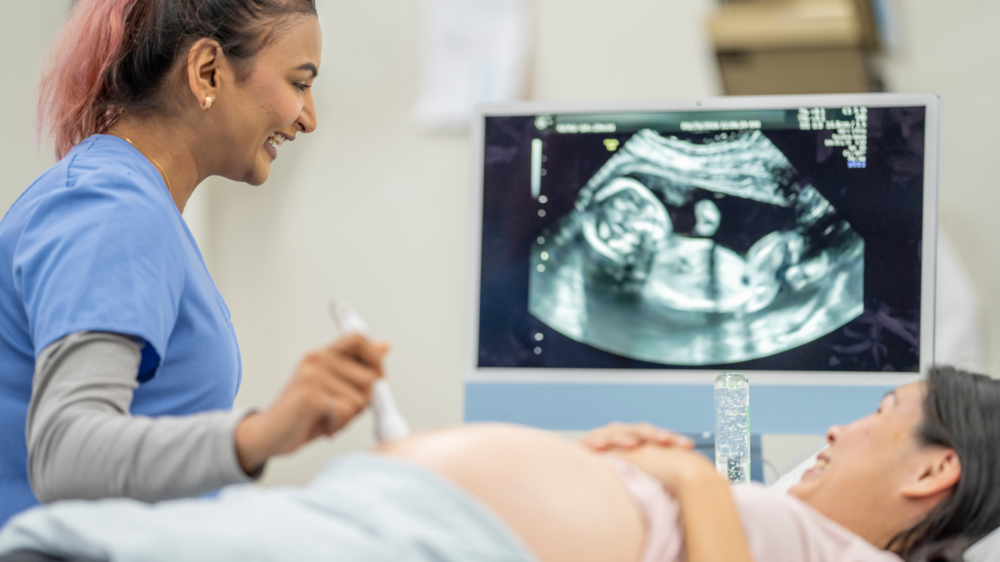

Why Babies Grow in Spurts Instead of a Straight Line Inside the WombOnce you get pregnant, your baby’s growth doesn’t always happen in a consistent manner. Rather, they grow in spurts, periods of rapid development followed by slower phases. This is a usual pattern and crucial for healthy development. Knowing why babies follow such a growth pattern during pregnancy can make you feel calmer during ultrasounds. It also helps you understand what to expect about your baby’s size and weight. It can also assist you in taking better care of yourself, both physically and emotionally.